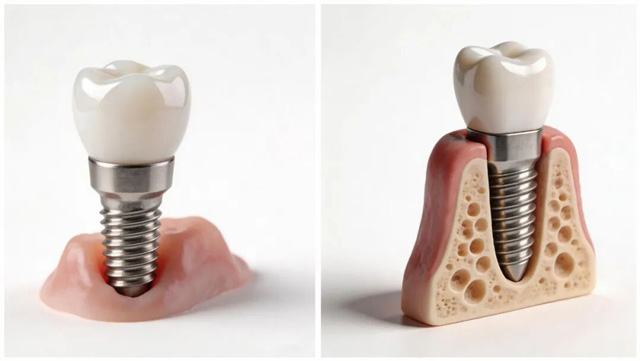

种植牙与牙槽骨,好比树与土!

种牙好比种树,牙槽骨如“土壤”,种植体如“树根”。健康的牙槽骨能为种植牙提供稳定支撑,实现骨结合并保障种植牙的长期使用。能承担“种牙大任”的牙槽骨是有标准的,对高度、宽度和骨密度都有一定要求。

如果在牙槽骨不符合要求的情况下植入种植体,会出现什么情况呢?

首先是种植牙的稳定性较差,不能满足正常咀嚼功能,严重者种植体可能会松动甚至脱落。上颌的种植牙如果骨量不足,还可能导致种植体暴露或穿通上颌窦,引发感染。